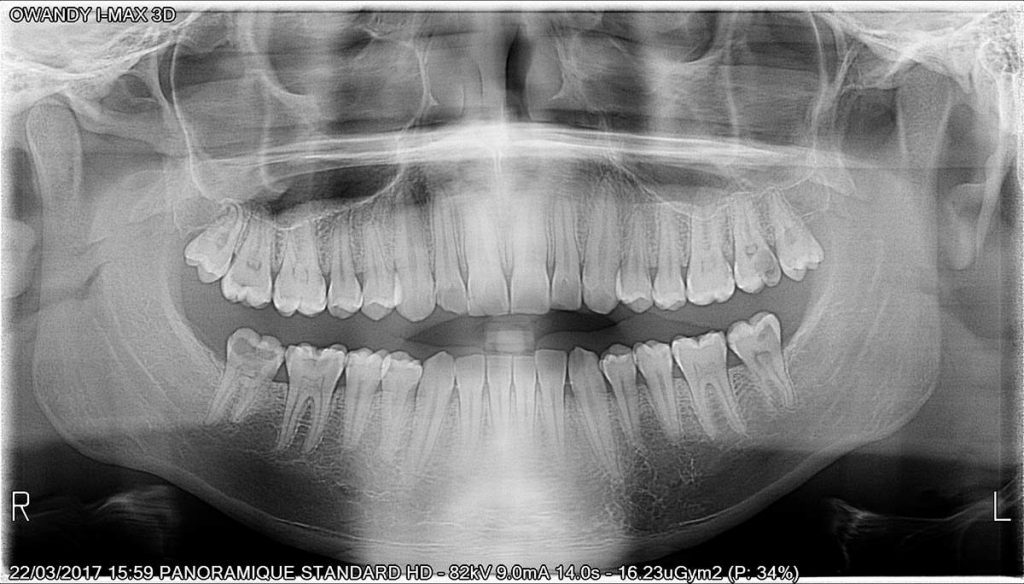

Calidad de imagen excepcional

I MAX-3D